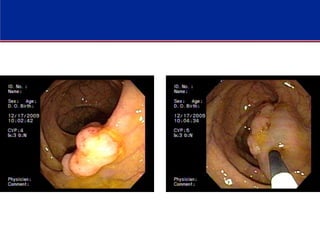

POLYPECTOMY

Endoscopic Removal of Large Colon Polyps

Endoscopic Mucosal Resection (EMR)

Endoscopic Submucosal dissection (ESD)

- ESD is a variant of EMR in which a specialized

needle knife is used to dissect lesions from the

submucosa. The advantage of ESD is that it often

permits removal of large sessile polyps en bloc (eg. in

one piece), whereas EMR often removes the polyp

piecemeal.